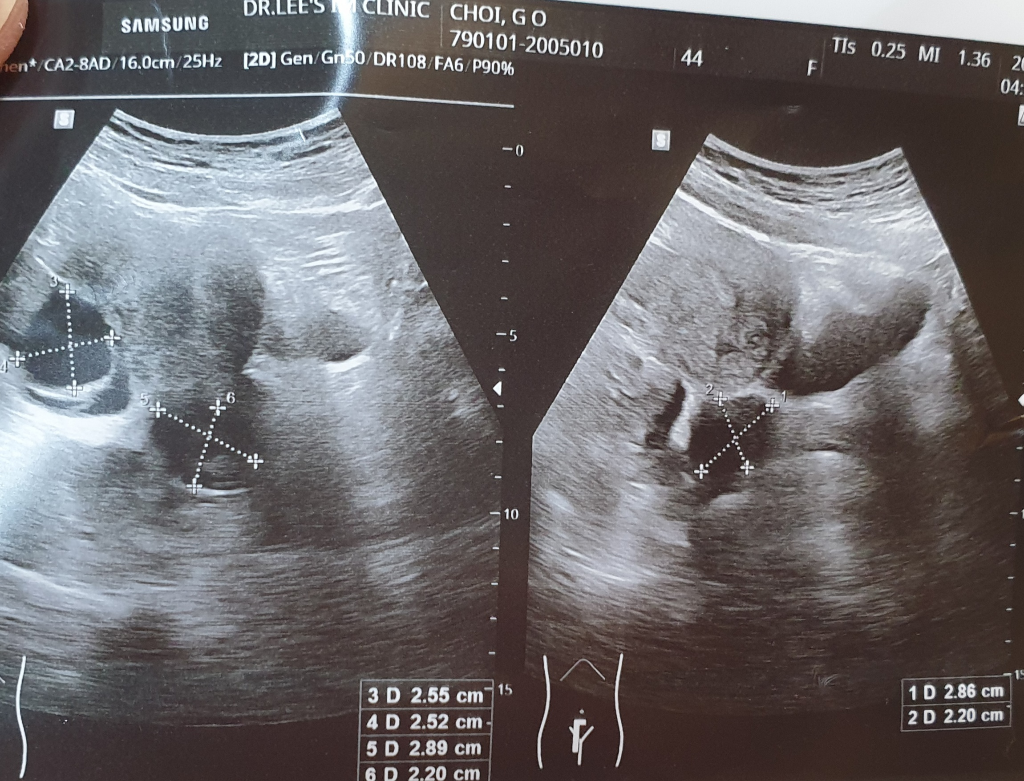

, "물혹"이라고 표현하신 것은 대부분 난소나 자궁 주변에 발생하는 낭종을 의미할 것 같습니다.

난소 낭종: 난소 낭종은 난소 내부나 표면에서 발생하는 액체로 찬 낭입니다. 대부분의 난소 낭종은 성인 여성 중 많은 사람들에게서 발견되며 대부분 증상이 없어 진단을 받지 못하는 경우가 많습니다. 대부분의 난소 낭종은 양성이지만, 악성으로 발전할 가능성도 있습니다.

자궁내막증: 자궁 경부에 "낭종"이 발견되면 자궁내막증의 가능성도 있을 수 있습니다. 자궁내막증은 자궁 내막이 자궁 밖에서도 발견되는 상태를 말합니다. 이것은 통증이나 월경 이상, 불임 등 다양한 증상을 유발할 수 있습니다.

난소 낭종: 대부분의 경우 치료가 필요하지 않을 수 있습니다. 하지만 크기가 크거나 증상이 나타나는 경우, 악성으로 의심되는 경우에는 수술적 제거가 필요할 수 있습니다.

우선 산부인과에 내원하시어 질초음파 등을 통해 정확한 위치 및 크기를 확인해 보시는 것이 좋겠습니다.